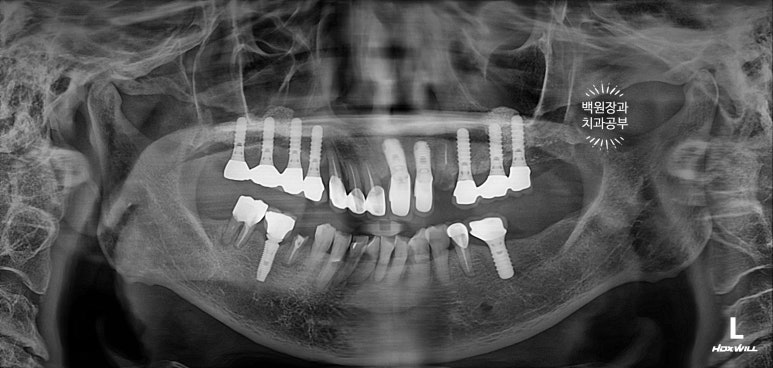

잘 보시면, 임플란트가 총 위턱에 9개, 아래턱에 2개 되어있는데 대부분이 아주 유명한 외국 임플란트 제품들입니다. 특히나 위턱 어금니는 스트라우만 standard 제품으로, 제가 가장 신뢰하는 제품 중 하나입니다.

처음 오셨을 때, 치과용 파노라마 사진에서 파란색 화살표로 표시해둔 두 치아 - 왼쪽 위 송곳니와 오른쪽 아래 작은어금니가 뿌리만 남아있는 상태로 내원하셨어요.

특이할만한 점이, 두 치아 모두 신경치료와 크라운 치료를 받았던 치아였다는 것... 역시나 신경치료는 치아 건강에 그리 좋지 않음을 알 수 있습니다..